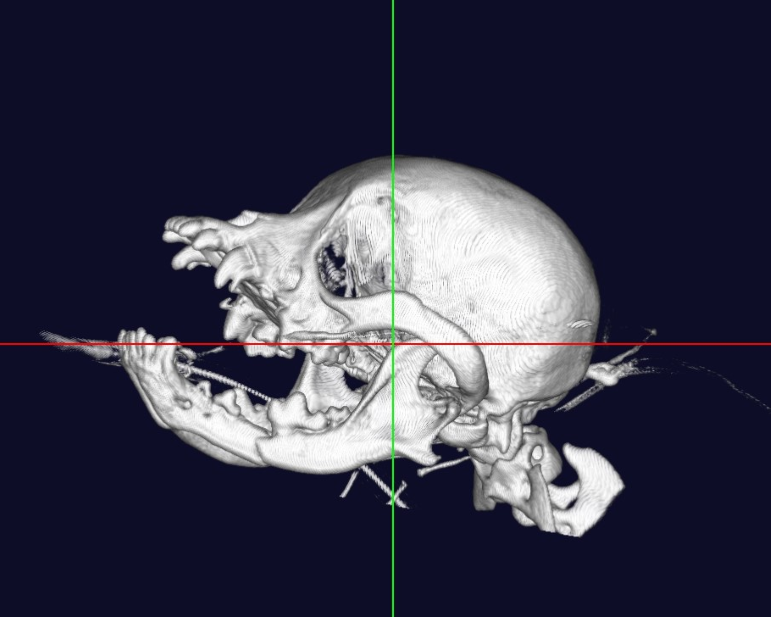

下顎骨 骨折

猫 頭部CT